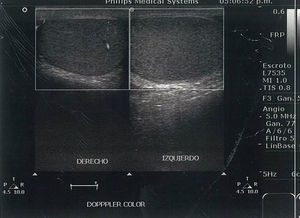

Los estudios de laboratorio únicamente con leucocitosis. El ultrasonido doppler testicular reportó cambios sugestivos de torsión testicular (figs. 1–3). Se realizó tratamiento quirúrgico de urgencia el mismo día de su admisión. Los hallazgos fueron un testículo izquierdo necrótico, con rotación de 360° del cordón espermático (fig. 4), por lo cual se realizó orquiectomía izquierda. El estudio histopatológico reportó infarto hemorrágico testicular. Durante la convalecencia no presentó complicaciones y fue egresado al día siguiente de su tratamiento quirúrgico.

La exploración física tiene un papel importante en el diagnóstico de la torsión testicular. Rabinowitz et al.7, en un estudio de 245 niños con escroto agudo, observaron una correlación del 100% entre la presencia del reflejo cremasteriano y la ausencia de torsión testicular, y concluyeron que la presencia del reflejo cremasteriano es el hallazgo clínico más valioso para descartar torsión testicular y su ausencia aumenta la sospecha diagnóstica. El estudio de imagen utilizado en nuestro medio para confirmar el diagnóstico fue el ultrasonido doppler, el cual tiene una sensibilidad del 96.8%, especificidad del 97.8%, un valor predictivo positivo del 92.3% y un valor predictivo negativo del 99.1%. Con esto se concluyó que la evaluación clínica, aunada al ultrasonido doppler, es una técnica fiable para la identificación de la torsión testicular8. Estas 2 herramientas fueron las que nos llevaron al diagnóstico de la enfermedad de nuestro caso aquí presentado. Si existe una alta sospecha de torsión testicular, a pesar de que la historia clínica, el examen físico, así como los estudios de imagen sean normales, se recomienda realizar exploración quirúrgica, con el fin de evitar la complicación más significativa como es la pérdida de testicular9. El desenlace de nuestro caso no fue la deseada, ya que el paciente se presentó a nuestra unidad hospitalaria con más de 12 h de evolución desde el inicio de su sintomatología, y perdió el testículo afectado. Existe literatura que reporta una tasa de orquiectomía en México hasta del 95%, lo cual es una cifra sumamente elevada10. Esto es un reflejo de la alta pérdida testicular en nuestro país.

Es importante destacar que esta entidad también puede presentarse en el periodo perinatal, lo que representa el 12% de todas las torsiones testiculares de la infancia; se divide en 2 categorías principales, una prenatal o intrauterina y la posnatal, la cual se presenta dentro del primer mes de vida. El manejo más adecuado aún es tema de controversia, sin embargo, ante la sospecha, se recomienda realizar tratamiento quirúrgico inmediato, ya que los estudios de imagen tienen limitaciones en este grupo de edad. Se recomienda la exploración quirúrgica del lado afectado y orquidopexia contralateral, debido al riesgo de presentar torsión testicular contralateral asincrónica11,12 (fig. 3).